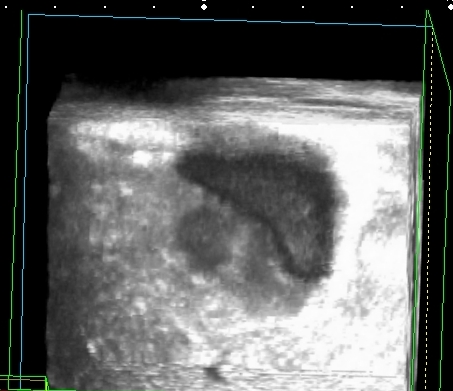

На УЗИ рядом с желчным пузырём определяется овоидное образование солидной струкутры с чёткими контурами.

При ЦДК кровоток в образовании не регистрировался, свободной жидкости в брюшной полости не было.